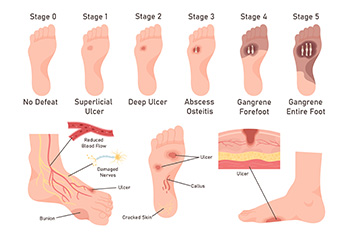

Managing Diabetic Foot Ulcers

Managing Diabetic Foot UlcersDiabetic foot ulcers are open sores or wounds that commonly occur on the bottom of the foot in people with diabetes. They are caused by poor circulation, nerve damage or neuropathy, high blood sugar levels, and repetitive pressure or...Wound Care

Wound CareDiabetics must be wary of all wounds, regardless of depth or size. Diabetes, a chronic disease in which the body cannot properly use glucose the way it normally would, causes various complications that make wounds difficult to heal. Nerve damage or...